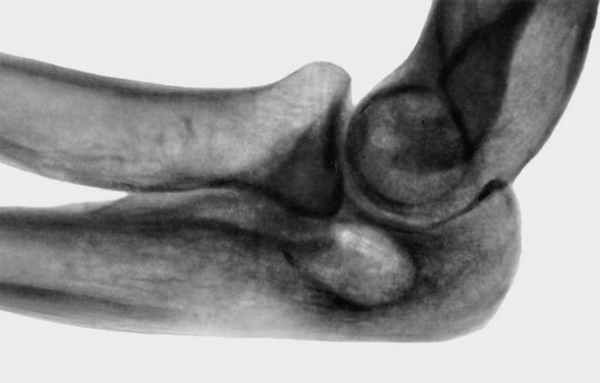

Рентгенограмма локтевого сустава (боковая проекция) при туберкулезном остите проксимального эпифиза локтевой кости: виден овальный деструктивный фокус; суставная щель сужена, что свидетельствует о переходе процесса на локтевой сустав">

Рис. 2. Рентгенограмма локтевого сустава (боковая проекция) при туберкулезном остите проксимального эпифиза локтевой кости: виден овальный деструктивный фокус; суставная щель сужена, что свидетельствует о переходе процесса на локтевой сустав.